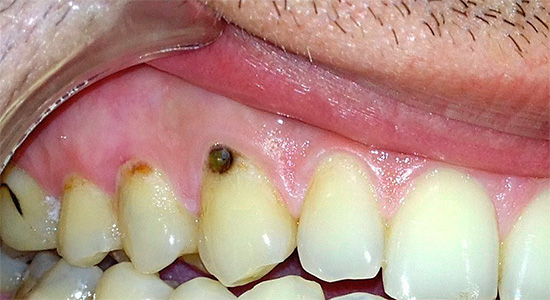

Con la posizione aperta della carie di cemento sui denti anteriori in combinazione con la carie cervicale, di norma, già allo stadio di un punto cariato senza una cavità cariata e nessun sintomo, si possono sospettare seri problemi e consultare un medico. Inoltre, in questo caso stiamo parlando della comodità di comunicare con i propri cari, amici, colleghi e altre persone. La comparsa di punti scuri, una sfumatura gessosa di smalto, le sue crepe e le schizzi al bordo con la gomma consentono di determinare la carie di cemento nella fase iniziale di sviluppo, quando può ancora "sfondare" nell'area subgengivale.

Con estese cavità carie che si estendono dalla superficie esterna del dente più in profondità nelle gengive, si verificano solitamente reazioni a freddo, caldo, dolce, acido, nonché una sensazione di indolenzimento, dolore durante il cibo. Spesso la gomma si allontana dal dente così tanto che sotto di esso è visibile l'area interessata del cemento radicolare e la radice stessa. In tali casi, è necessario consultare immediatamente uno specialista per ulteriori studi e conferma della diagnosi.